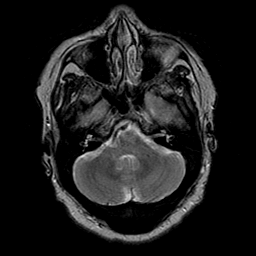

Cerebral hemorrhage, MR Study mr-t2 -- Slice #6

[Home][Help][Clinical] Slice 6